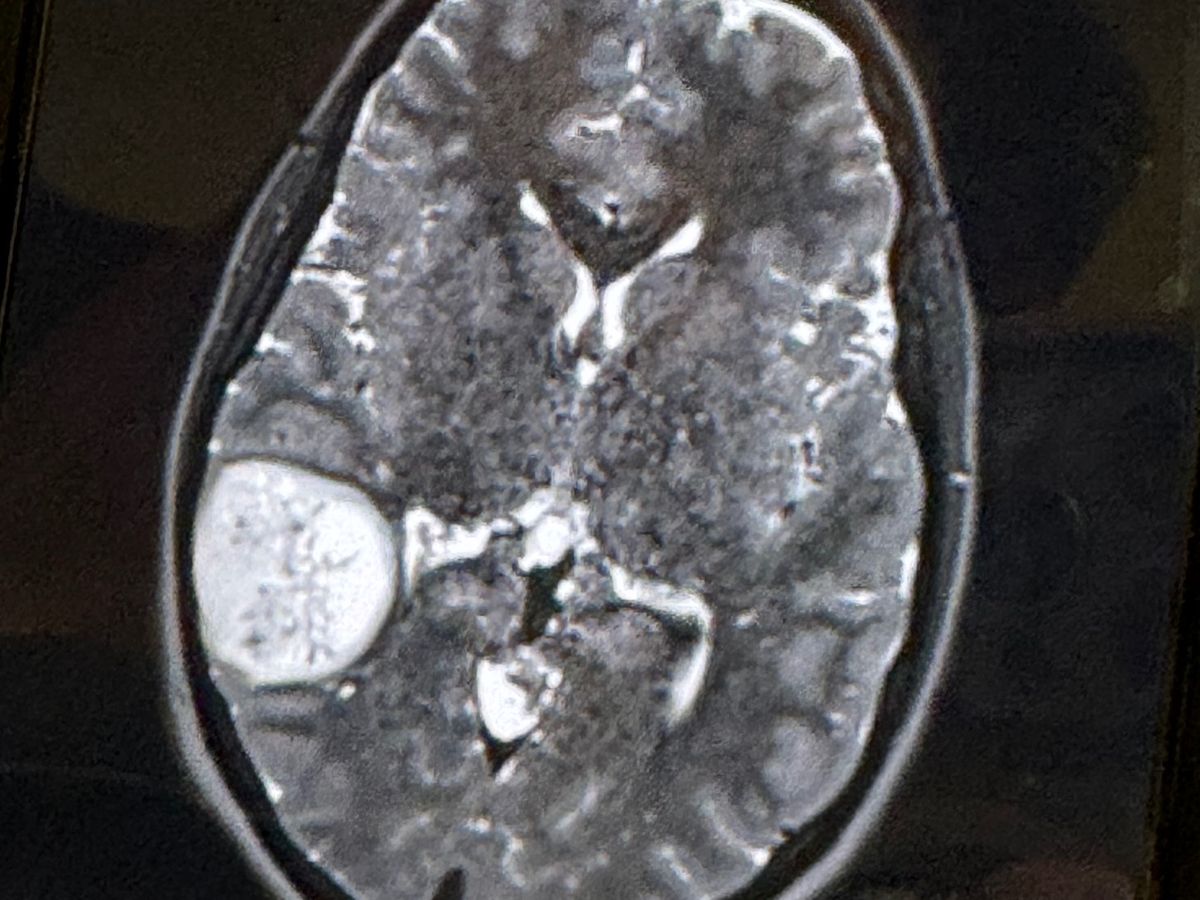

As most of you know Farrah underwent surgery in February due to a severe brain tumor that caused a seizure and resulted in a motor vehicle accident. Therefore she has no car and is not able to drive or work for a long time now. She has completed her first round of chemotherapy and radiation that consisted of going to Austin everyday Monday-Friday for 3 months. To prepare for further and more aggressive chemotherapy she just had surgery on August 21st to have a port placed where the chemo will be injected a few times a month along with labs that have to be done weekly in austin and Harker Heights. The cancer has not come back nor spread but with the type that she has they say will never be completely gone and has to be kept stable. Subjectively because of her medical condition and concurrent chemo and radiation treatments she suffers from: seizures, headaches, difficulty with word finding, weakness in the right side, forgetful, distracted, decreased focus, nausea, irritability, fatigue and hairloss. Her activities are limited because she is not suppose to drive, has difficulty time maintaining a consistent schedule. Again not able to work so can use all the help possible with daily responsibilities and or expenses. Thanks for all the prayers and support here on out

Farrah Carnes is a single mother of three grade school girls and a resident of Lampasas, Tx, she is now at home recovering from a severe brain tumor that they found after a car accident that totaled her car. Farrah had a seizure Friday 2/9/24 (Her birthday to be exact) which caused a car accident! She was then rushed to seton in Harker Heights where they did a CT SCAN and MRI which showed a mass/tumor on the right side of her brain! They transferred her to Seaton medical center in Round Rock where they have a neurosurgeon and better team! They have decided instead of just doing a biopsy which would only be taking part of it at the time and could just cause spreading and bleeding that they are actually going in to remove as much as they can to also send off to see what and if she will need radiation and/or chemo! Surgery has went well and the doctors believe to have removed the tumor in its entirety but aren’t sure if it’s cancerous or not yet. She has begun recovery very well and is able to talk and walk with the help of a walker so today 2/15/24 the doctors have released her to go home. Farrah is going to need extended supervision and will not be able to drive on her own for about 6 months. She is very grateful for everything anyone can help with as she continues on this long road of recovery. Thank you to everyone in advance!!